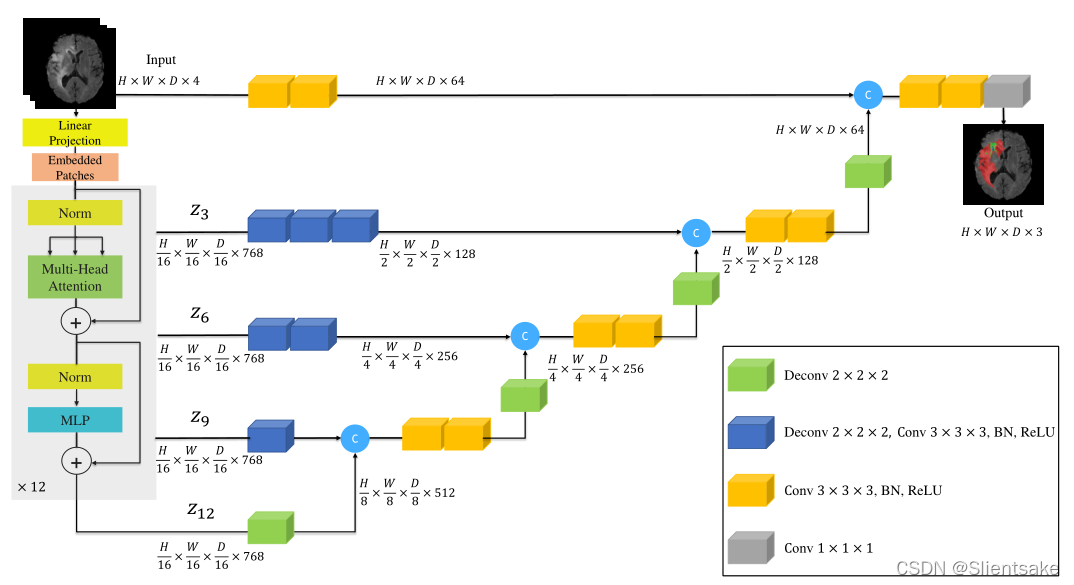

在图2中展示了所提议的模型的概述。UNETR采用收缩-扩展模式,由一堆Transformer组成,编码器通过跳跃连接到解码器。Transformer工作在输入嵌入的一维序列上,这是NLP中常用的方法。同样,将三维输入体积 ,分辨率(H,W,D)和C输入通道划分为平坦的均匀非重叠斑块 ,创建一个一维序列,其中(P, P, P)表示每个patch的分辨率, 为序列的长度。

图2:UNETR架构概述。将一个三维输入体(如MRI图像的C= 4通道)划分为一系列均匀的不重叠的patch,并使用线性层投影到嵌入空间中。该序列与位置嵌入一起添加,并用作Transformer模型的输入。Transformer中不同层的编码表示通过跳跃连接提取并与解码器合并,以预测最终分割。

图1所示:UNETR的概述。提出的模型包括一个Transformers编码器,它直接利用3D patch,并通过跳跃连接 连接到一个基于CNN的解码器。